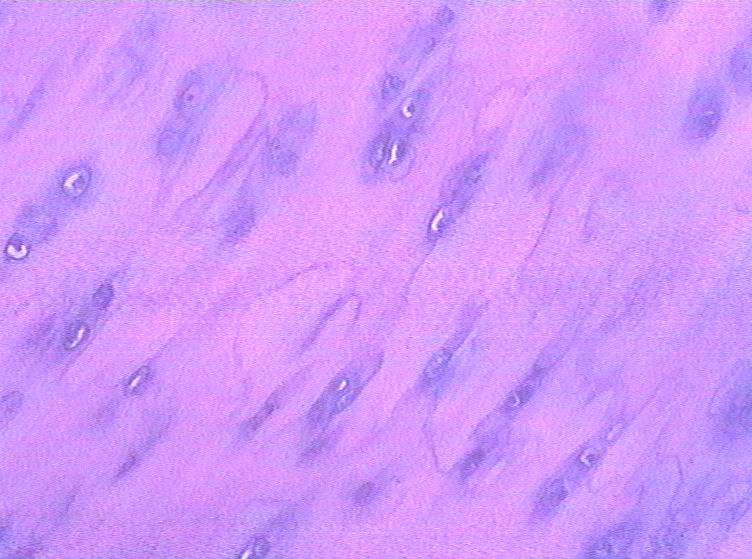

男,48岁,肿块直径1.5CM。

高疑软骨肉瘤,请同行会诊。